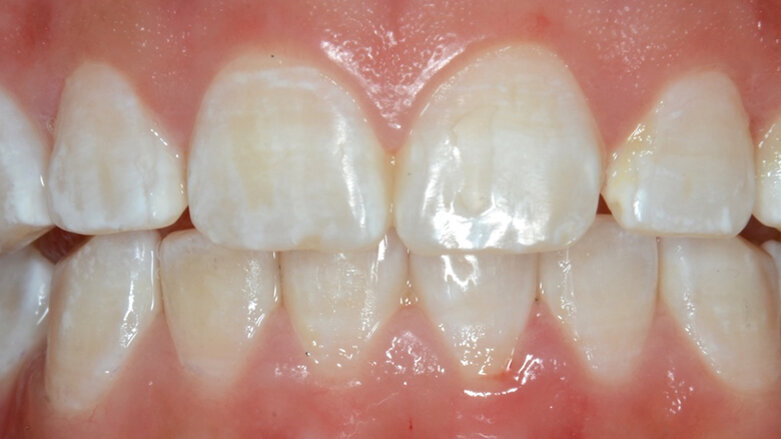

Respondiendo a estas necesidades, hoy contamos con procedimientos estéticos seguros y fáciles de obtener, siempre y cuando trabajemos con productos que tengan una estabilidad química y un adecuado porcentaje para cada procedimiento. Esto representa un desafío para nosotros los dentistas cuando nos encontramos con manchas blancas, amarillas o marrones, sean de origen traumático, por descalcificación o por un defecto generado durante la formación del diente, como puede ser la ingesta excesiva de flúor durante la formación de éstos (fluorosis), ya que nuestros pacientes son muy jóvenes y debemos preservar al máximo la estructura dental.

Dentro de las alternativas que tenemos en la Odontología Estética Mínimamente Invasiva, está la microabrasión, en situaciones donde las alteraciones del esmalte sean superficiales, a menos 200µprofundidad, incluyendo decoloraciones causadas por fluorosis que no hayan respondido a aclaramientos realizados con técnicas ambulatorias. La microabrasión es un procedimiento de la odontología cosmética que se utiliza para mejorar la apariencia de los dientes, el cual puede ser mecánico (óxido de aluminio) o químico (ácido clorhídrico al 6,6%), pasta que contiene partículas de carburo de silicio hidrosoluble, através del cual removemos la parte superficial del esmalte. En algunos casos, como en el presente, fue necesario acompañar la microabrasión con un aclaramiento ambulatorio a concentraciones acordes al grado de complejidad y edad del paciente.

Paciente femenino, 20 años, presencia de manchas blancas generalizadas, no presenta sensibilidad, no se ha realizado ningun tipo de aclaramiento dental (Foto 1).